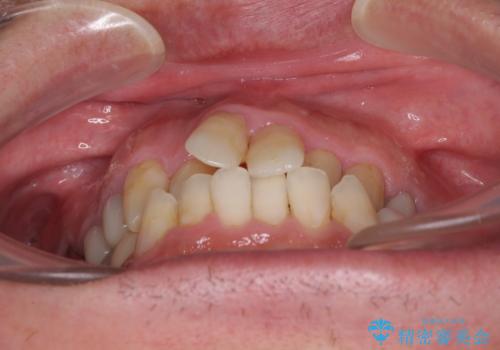

飛び出した前歯と目立つ銀歯 矯正とセラミックの総合歯科診療

- 飛び出している上顎前歯と、奥歯に多くある銀歯を気にして来院された患者様です。

マウスピースで矯正を行いたい反面、一旦早めに前歯を整えたいというご希望があったため、まずは上顎前歯をワイヤー装置で整え、その後インビザラインにて仕上げていくこととしました。